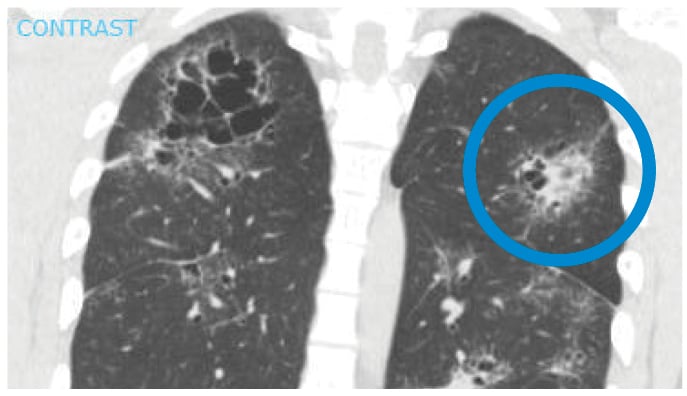

On initial evaluation, his pulse was 126 beats/min and temperature was 38.6°C. He had right facial palsy, bilateral ankle periarthritis, active bilateral anterior uveitis, and sequelae of prior panuveitis. Initial laboratory studies were notable for maximally dilute urine. Chest X-ray and computed tomography (CT) scanning showed interstitial infiltrates, bilateral hilar lymphadenopathy, multifocal peribronchovascular bronchiectasis, and “galaxy signs" (Fig. 1). Ankle radiographs were unremarkable.

Figure 1: CT scan of the chest showing galaxy sign in sarcoidosis: an irregular lesion formed by dense, central coalescence of granulomas associated with diffuse granulomas in the periphery, radiographically resembling a galaxy.